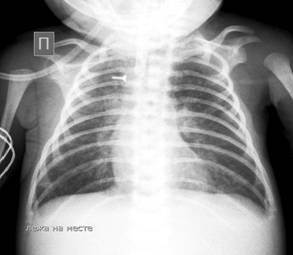

Материалы и методы. Описанный клинический случай сочетанных множественных пороков развития, ребенка Г., в возрасте 3 месяцев находящегося в ОРИТ КГП «ОДКБ».  Данному ребенку были проведены комплексное обследование, в том числе R-графия ОГК, НСГ. (Рис.1)

Рисунок №1